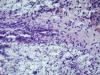

Образование левой ветви легочного ствола |

Макро фотографии к сожалению нет. Был фрагмент легочного ствола с бифуркацией, один сосуд с обычными стенками, макро без изменений, в второй неравномерно утолщен, как бы часть сосудистой стенки обычная, а часть утолщена и частично выпирала в просвет.

Эндотелизированный и реканализованный тромб трудно с чем-либо спутать. Теперь надо двигаться дальше: катамнез, причина, источник ТЭЛА и т.д. К примеру, при АФС ответ очевиден, а при "ТЭЛА" вследствие патологии ЛА - думать о сосудистом процессе.